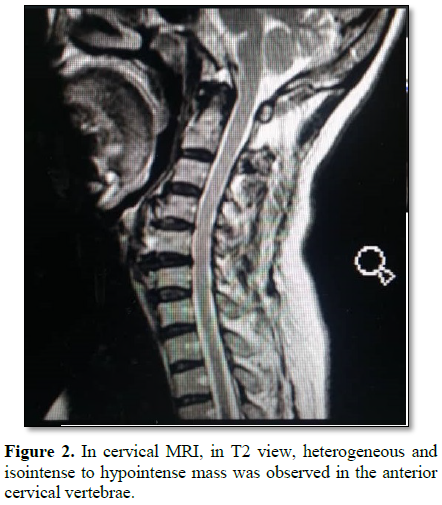

The patient was a 40 year old woman suffering from chronic neck pain and dysphagia and shortness of breath. She was under investigation and imaging to diagnose digestive and respiratory diseases and pharyngeal disease that was healthy. But in the lateral cervical x-ray, a bone mass adhered to the anterior cervical vertebra was observed (Figure 1). This patient was not obese (BMI=18.5) had no history of any rheumatoid, cardiovascular and metabolic disease and there was no evidence of disease in the studies. She did not have any neurological and motor disorder and sphincteric disorder. In the lateral cervical x-ray, a large calcified anterior ligamentous mass was observed in anterior part of body of C4, C5 and C6 vertebrae (Figure 1), causing partial obstruction of esophagus. In cervical MRI, in T1 view, isointense to hyperintense mass were observed on the anterior C4, C5, C6 and in T2 view, heterogeneous and isointense to hypointense mass was observed in the anterior cervical vertebrae (Figure 2). In thoracic spine and lumbosacral spine x-ray, bone mass was seen in anterior lumbar vertebrae (L2 and L3) (Figure 3), which had not caused any symptoms in the patient. This patient was underwent surgery and the anterior neck calcification was removed (Figure 4) and after a few days symptoms of dysphagia and dyspnea were resolved.